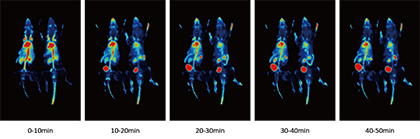

- 动态成像技术

同步实现药物注射和数据采集。实时跟踪示踪剂在动物体内的动态分布,精确分析药物的代谢过程。